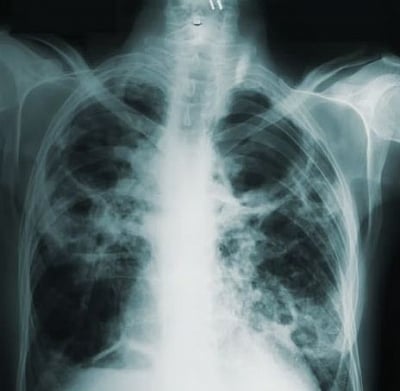

The software analyses chest CT scans and use deep learning algorithms to accurately diagnose the disease. With an accuracy rate of 97.86 percent, it's currently the most successful Covid-19 diagnostic tool in the world, said the team of the University of Leicester.

"Research focuses on the automatic diagnosis of Covid-19 based on random graph neural networks. The results showed that our method can find the suspicious regions in the chest images automatically and make accurate predictions based on the representations," said Yudong Zhang, Professor of Knowledge Discovery and Machine Learning at the varsity.

"The accuracy of the system means that it can be used in the clinical diagnosis of Covid-19, which may help to control the spread of the virus. We hope that, in the future, this type of technology will allow for automated computer diagnosis without the need for manual intervention, to create a smarter, efficient healthcare service," Zhang said.